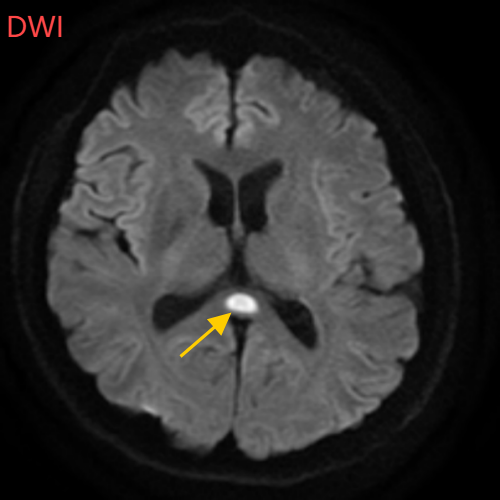

医生摇摇头,经过头部磁共振平扫、弥散、增强影像等检查,医生诊断,小董是得了一种比较少见的病症:可逆性胼胝体压部综合征。

如果把大脑比作一座城市,胼胝体就是连接左右脑的“跨海大桥”,而胼胝体压部正是桥上的“核心枢纽”。当它因酒精、熬夜或感染“肿了”,大脑信号就会“堵车”,引发一系列“故障”。

“压部”病变:胼胝体压部是大脑里的“视觉总监”,眼睛所看到的信息传送到大脑后,由它负责反应整合成图像在脑海中呈现。“压部”发生病变后,就像电视机信号接收不良,屏幕出现雪花一样,眼睛视物就会受到影响。

除了“压部”,胼胝体的其他部位也有病变,所以小董才会出现幻听、手抖等症状。